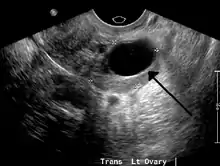

غالبية أكياس المبايض متعلقة بعملية التبويض بكونها إما كيسة جريبيه أو كيسة الجسيم الأصفر. تتضمن الأنواع الأخرى أكياسأ بسبب بطانة الرحمة المهاجرة، أو كيسة جلدانية،أو ورم غُدًّيٌ كيسي. في متلازمة تكيس المبايض تظهر العديد من الأكياس الصغيرة في كلا المبيضين. و قد ينتج التهاب في الحوض بسبب ظهور هذه الأكياس. يتم تشخيص هذه الحالة عن طريق فحص الحوض باستخدام الأشعة فوق الصوتية أو عن طريق إجراء فحوصات أخرى لجمع مزيد من المعلومات عن الحالة.

غالباً ما يتمّ تشخيص سرطان المبيض إما عن طريق الأشعة فوق الصّوتيّة، أو الأشعة المقطعيّة، أو الرنين المغناطيسي، وتكون مرتبطة بأعراض إكلينيكية وفحوصات الغدد الصمَاء تكون ضرورية بحسب الحالة.